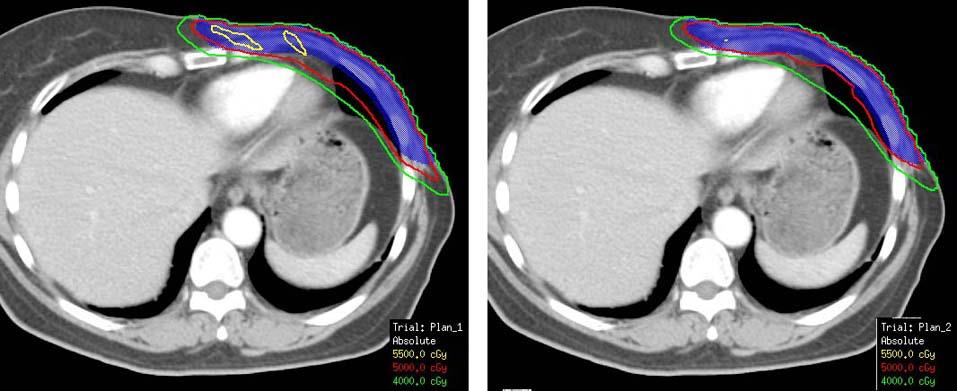

Che CHEN,Dehong LUO,Huangfei YU,Qin ZHANG,Xiaochi HU,Shenghua YU,Yajun. LI.

Clinical Application of automatic delineation in whole breast radiotherapy with simultaneous integrated boost to the medial tumor beds

[J]. The Journal of Practical Medicine, 2024, 40(17): 2406-2411.